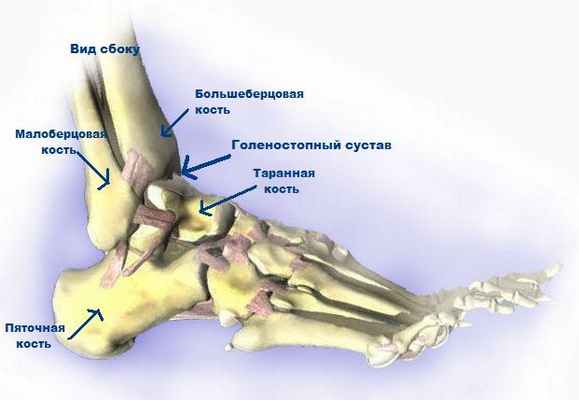

Голеностопный сустав состоит из трех костей:

Двух гостей голени (малоберцовой кости и большеберцовой кости)

Кости стопы (таранной кости), расположенной между костями голени и пяточной костью

Эти три кости связаны несколькими связками, которые образуют кольцо и обеспечивают устойчивость лодыжки. При переломах кольцо часто разрывается в нескольких участках. Например, при переломе одной из костей обычно одновременно происходит разрыв связки. Если при переломе происходит разрыв двух или более структур кольца, лодыжка теряет устойчивость.

Анатомия лодыжки